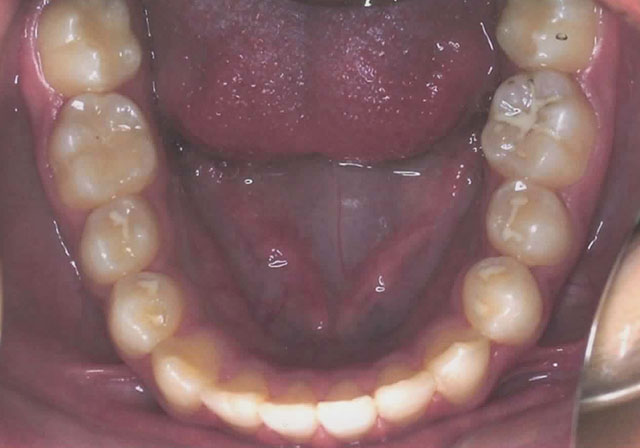

After